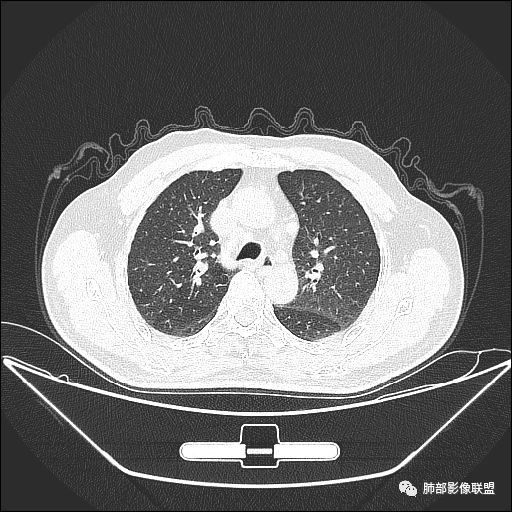

入院CT

老年男性,咳嗽一月,间断伴红色血痰

PPD阳性

从临床是否要考虑结核,但这个年龄恶性也是高危

影像上叶后段支气管壁增厚,附近似有淋巴结有气体潴留

左下叶背段小结节,舌段索条,内似有扩张支气管

肺门纵隔多发淋巴结肿大,内有钙化灶

我们现在看主病灶,病灶紧贴叶裂:

我想看冠状位,就是看它长轴、病灶的整体形态

外围大、内带小

这时候我认为支气管最重要

支气管进入其中,远端粘液栓

我认为鉴别:结核?腺癌?